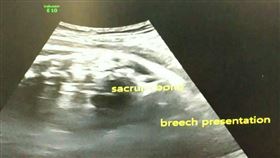

胎位不正

36周孕婦胎位不正 醫「隔肚皮」喬回原位

孕婦最怕胎位不正,中國湖南日前就有一名懷孕36周的准...

寶寶胎位不正將臨盆 護理師硬凹神明

孕媽美雅36歲是位護理師,頭胎自然產一位小姊姊,第二...

神奇!胎位不正 艾草燻寶寶「歸位」

胎位不正一定要剖腹嗎?33歲的林小姐懷孕7個多月後,...

寶寶伸出小腳ㄚ 救護員即刻接生救命

台南一名孕婦懷孕第三胎,因為寶寶胎位不正,原本想進醫...